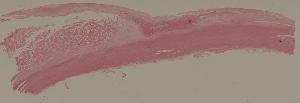

9. Healing of skin by first intention